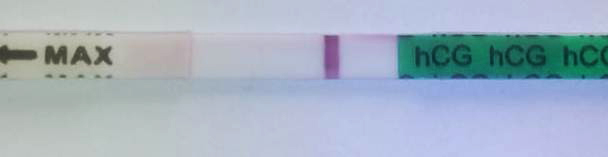

замочила только что....и снова непонятки...что это? реагент или проклевывается что то?....обеденный тест был вот таким

замочила только что....и снова непонятки...что это? реагент или проклевывается что то?....обеденный тест был вот таким

Видно хорошо, а нижний чистый 🤔

я наоборот на нижнем и увидела....сначала а потом побежала в аптеку за ещё одним...на нижнем четкая полоска но очень бледная,плохо виждно а вот вечерний похож на реагент..растекся весь

Да, так видно, пусть будет оно!

Проклевывается. У меня так было в 1 беременность

Есть вроде на обоих но тесты тупаки конечно

Фигасе. Тут уже точно всё понятно.